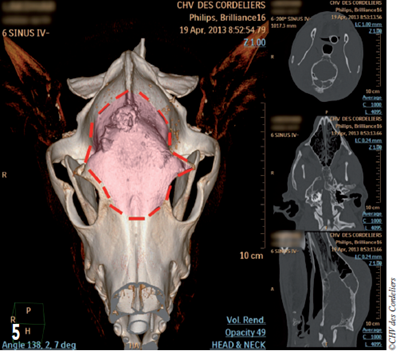

Une crâniotomie est réalisée en prenant des marges de 5 à 10 mm autour de la masse (photo 5).

Photo 5 : Délimitation de la craniotomie (en rouge) sur la vue tomodensitométrique préopératoire.